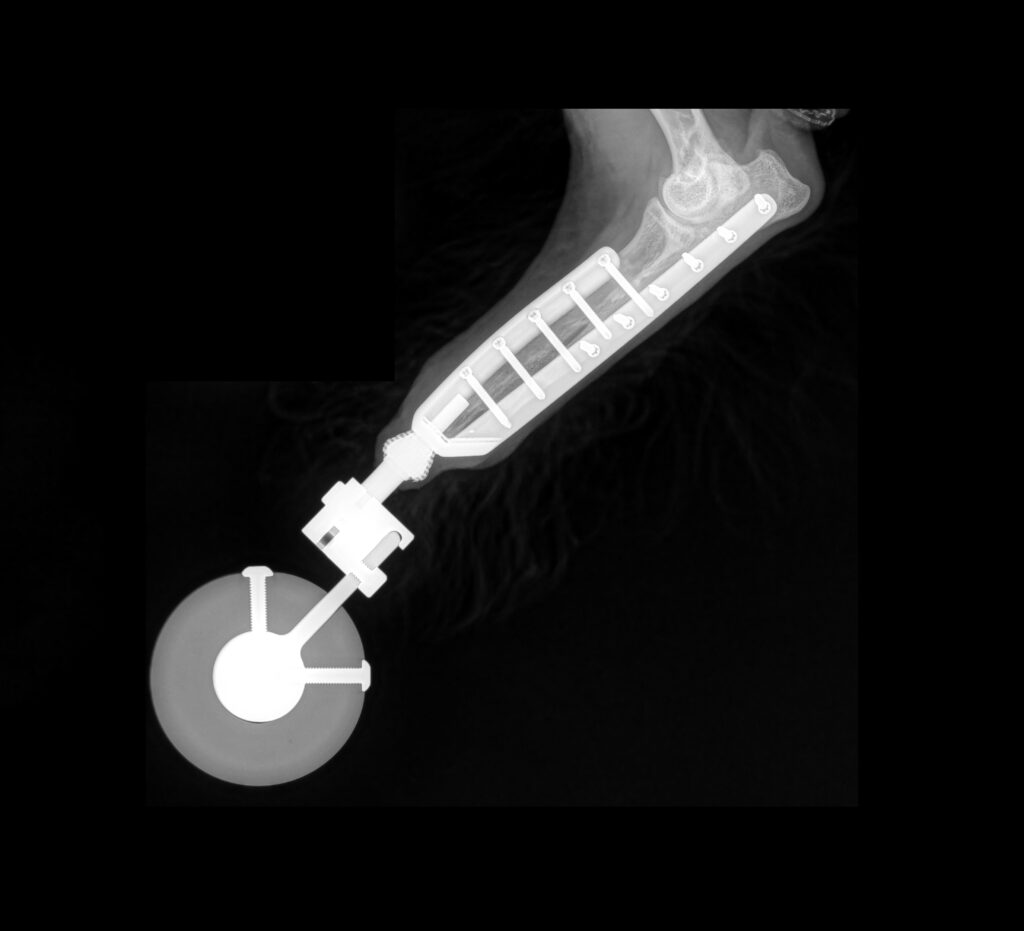

Limb sparing/salvage

Unique options to Fitzpatrick Referrals in limb sparing and salvage for treating trauma and cancer in the forelimb or hind limb.

Pablo’s bone transplant

Major Tom’s osteosarcoma

Sunny’s rotating hinge total knee replacement